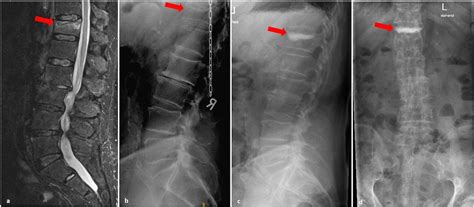

So, how do doctors actually diagnose an Ideckplattenfraktur LWK 1? Usually, it starts with a thorough physical exam and a review of the patient’s medical history. The doctor will ask about the mechanism of injury – how did the fracture occur? They’ll also assess the patient’s symptoms, such as the location and severity of pain, any neurological deficits, and any other associated injuries. Imaging studies are essential for confirming the diagnosis and determining the extent of the fracture. X-rays are often the first-line imaging test, as they can quickly and easily visualize the bones of the spine. However, X-rays may not always be sensitive enough to detect subtle endplate fractures. In these cases, a CT scan or MRI may be necessary. A CT scan provides more detailed images of the bony structures of the spine, while an MRI can visualize the soft tissues, such as the spinal cord, nerves, and ligaments. This is particularly helpful in identifying any nerve compression or other soft tissue injuries.

Surgery may be necessary in more severe cases, such as when the fracture is unstable, there is significant nerve compression, or non-surgical treatment has failed. The goal of surgery is to stabilize the spine, relieve nerve compression, and restore spinal alignment. There are several different surgical techniques that can be used, depending on the specific characteristics of the fracture. Spinal fusion is a common procedure that involves joining two or more vertebrae together to create a solid, stable segment of the spine. This can be done using bone grafts, screws, rods, and other hardware. Another surgical option is vertebroplasty or kyphoplasty, which involves injecting bone cement into the fractured vertebra to stabilize it and reduce pain. The choice of surgical technique depends on the individual patient’s needs and the surgeon’s expertise.